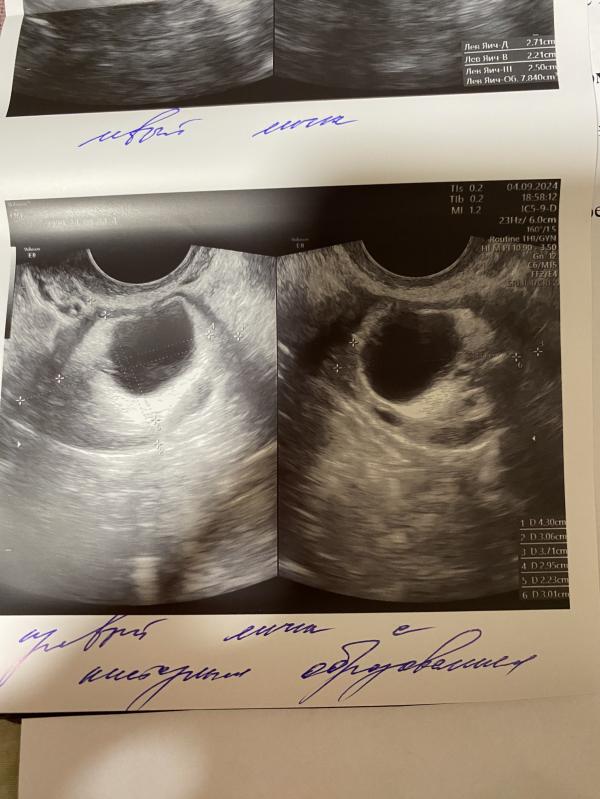

Так случилось, что у меня появилась киста , узнала я это в июле месяце , сделала узи и собственно там и сказали , но врач была не многословна, сказала только, что надо будет сделать после месячных узи ( месячных у меня не было на тот момент 5 месяцев , поэтому и пошла по врачам).

Вот благодаря таблеткам Силуэт , у меня пошли долгожданные месячные , и после них я побежала на узи, но результаты прошлого узи я забыла, так вот скажите пожалуйста , может кто-то разбирается , ес...